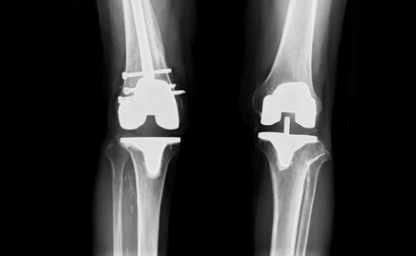

무릎 인공관절 수술은 손상된 무릎 관절을 제거하고, 이를 대신할 인공관절을 삽입하는 수술입니다. 주로 퇴행성 관절염, 연골 손상, 또는 무릎 관절의 기형으로 인해 무릎 기능이 심각하게 손상된 사람들에게 시행됩니다.

3. 수술 방식

- 부분 인공관절 수술과 전체 인공관절 수술에 따라 비용이 다릅니다. 부분 인공관절 수술은 무릎의 일부만 교체하는 방법으로, 비용이 상대적으로 저렴할 수 있습니다. 반면에 전체 인공관절 수술은 무릎 전체를 교체하는 방법으로, 더 복잡하고 비용이 높습니다.

최근에는 무릎 인공관절 수술의 기술 발전과 함께, 환자 맞춤형 수술법이 도입되고 있습니다. 이는 수술의 정확성을 높이고, 회복 속도를 빠르게 하는 데 도움을 줍니다.

- 로봇 수술: 로봇 보조 수술이 점점 널리 사용되고 있으며, 이는 수술의 정밀도를 높여 부작용을 줄이고 회복 기간을 단축하는 데 기여합니다.

- 맞춤형 인공관절: 각 환자의 무릎 형태와 상태에 맞춰 맞춤형 인공관절이 제작되어, 환자의 활동성과 수명을 더 연장시키는 기술이 발전하고 있습니다.